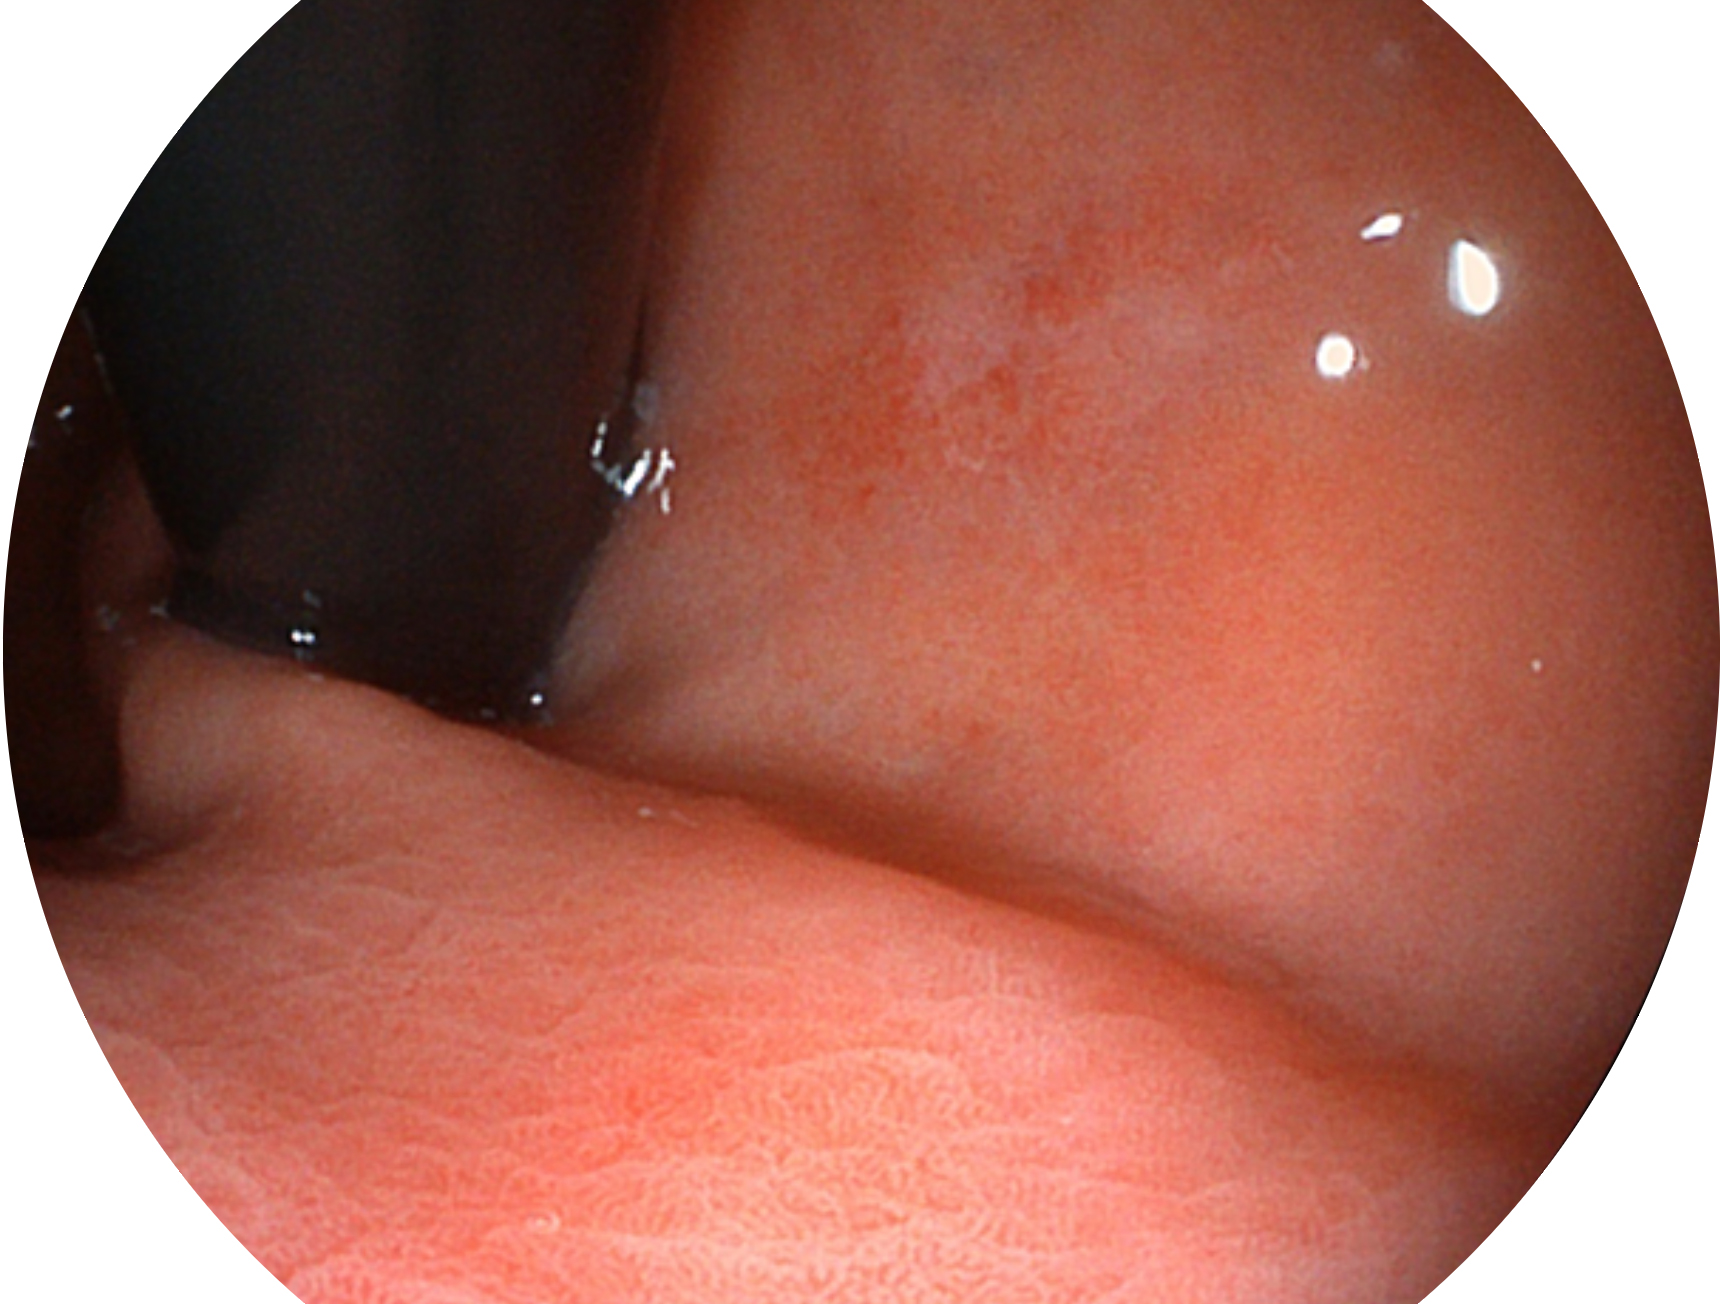

诸侯快讯官网新开发的内镜染色技术,主要是基于多波长LED 光源的开发,VLS-55Q 四波长LED 光源是由四个不同颜色的LED光按照相应照明模式所规定的特定发光比例进行合束后形成,合束后形成的照明光的光谱由红光、绿光、蓝光及蓝紫光这四个不同的波段范围构成。具有更高光谱自由度,通过光谱比例的控制,实现了聚谱成像技术,英文全称为“Spectral Focused Imaging, SFI”,缩写为“SFI”和光电复合染色成像技术,英文全称为“Versatile Intelligent Staining Technology, VIST”,缩写为“VIST”。